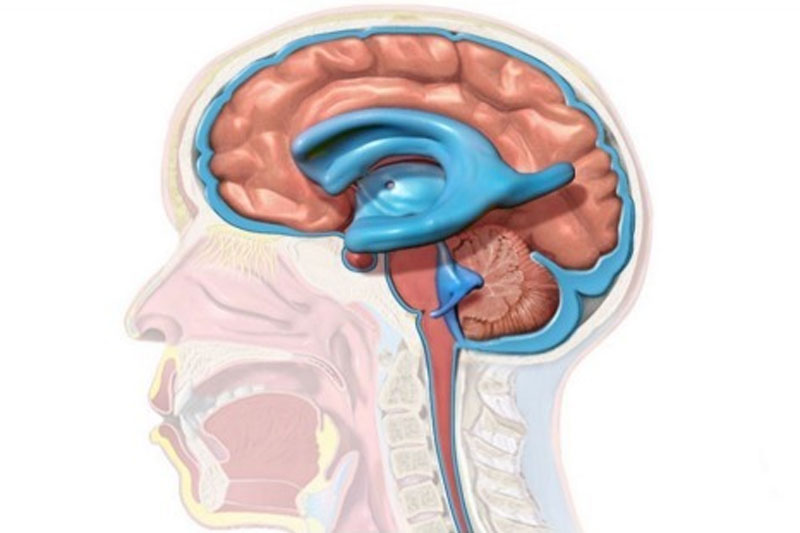

Hidrocefalia (hidro: água + céfalo: cabeça; água na cabeça) consiste no acúmulo do líquido cefalorraquidiano ou líquor nos ventrículos cerebrais (cavidades do cérebro). Esse acúmulo ocorre geralmente por obstrução da circulação do líquor através dos quatro ventrículos cerebrais. O excesso retido faz os ventrículos cerebrais dilatarem, provocando compressão e danos no tecido cerebral. A hidrocefalia pode afetar pessoas de qualquer idade, mas é mais comum nas crianças. Cerca de um em cada 1.000 bebês nascem com hidrocefalia.

O tratamento é cirúrgico por meio de derivação ventricular ou por restabelecimento da circulação liquórica por meio de tratamento endoscópico. A técnica mais utilizada é a derivação ventrículo-peritoneal que consiste em aliviar a pressão intracraniana desviando o excesso de líquor contido nos ventrículos cerebrais para a cavidade abdominal. Para tanto, um cateter passado por baixo da pele do pescoço e do tórax comunica o ventrículo cerebral com a cavidade abdominal. Uma válvula é interposta nesse cateter para controlar o fluxo do líquor entre as duas cavidades. Como o sistema de derivação é um tubo de silicone, ocorre frequentemente obstrução ou infecção como complicação do tratamento cirúrgico. Por tal motivo, os familiares devem estar atentos para que o quanto antes se tomem as devidas providências.

O outro procedimento cirúrgico é a terceiro-ventriculostomia. Por via endoscópica, o cirurgião faz uma perfuração no assoalho do terceiro ventrículo, restabelecendo a circulação do líquor represado.